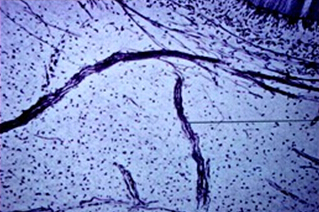

牙髓(pulp)是来源于外胚间叶的疏松结缔组织,位于由牙本质所形成的髓腔(髓室和根管)内。牙髓的主要功能是形成牙本质、营养、感觉、防御及修复。牙髓中的血管、淋巴管和神经仅通过根尖孔与根尖部的牙周组织相通连。

牙髓是疏松结缔组织,它包含有细胞、纤维、神经、血管、淋巴管和其他细胞外基质。牙髓组织可分为四层,即:

牙髓间质内主要是胶原纤维和嗜银纤维,而弹力纤维仅存在于较大的血管壁上。牙髓中的胶原纤维主要由I型和Ⅲ型纤维以55:45的比例所组成,纤维交织成网状。随着年龄的增加,胶原纤维的量逐渐增加,但其构成比则基本保持不变。嗜银纤维即网状纤维,为纤细的纤维,主要构成也是Ⅲ型胶原蛋白,分布于牙髓细胞之间。嗜银纤维只有在应用银染色时才能显示。其着色机制被认为与Ⅲ型胶原表面的蛋白多糖成分有关。牙髓也有少量Ⅴ型和VI型胶原。在牙本质形成的早期,在牙髓边缘聚集有粗大的科尔夫纤维束。